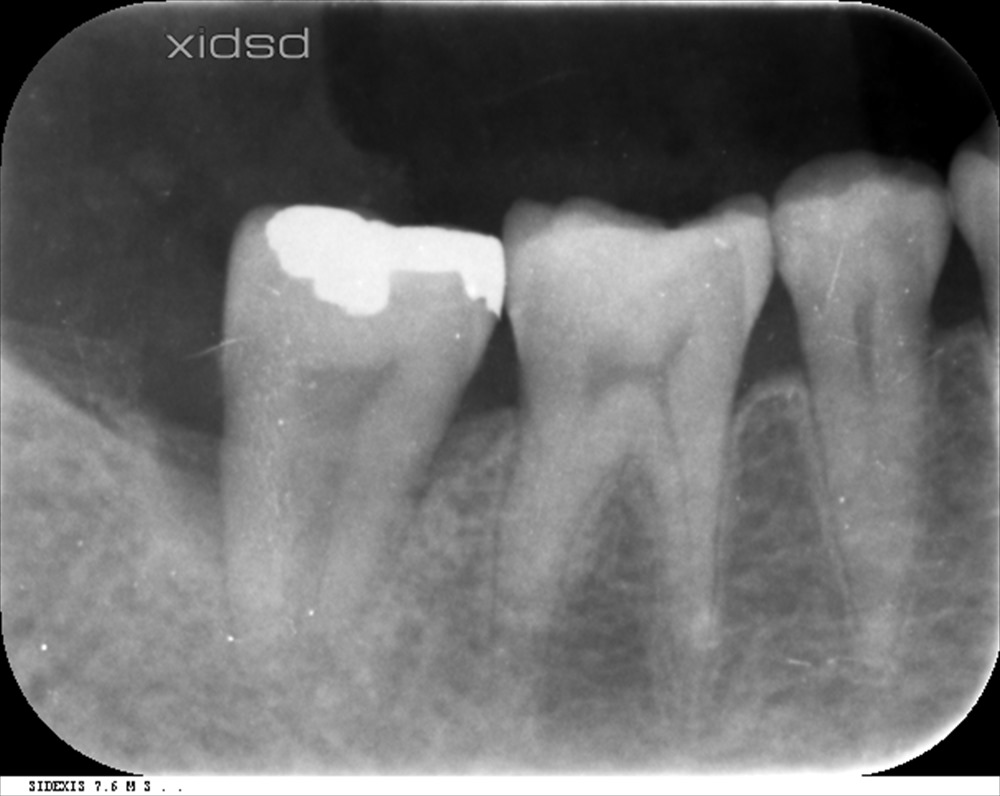

右下の一番奥の歯の後ろ側に10mmのポケットがありました。

この様な骨内欠損です。

マイクロスコープとエルビウム・ヤグレーザーでデブライドメントと無毒化を図りました。